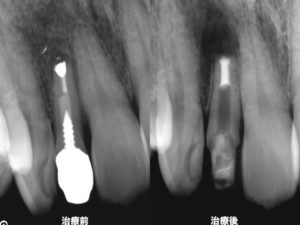

矯正の先生からは、内部吸収をしているので治してほしいと言われてたのですが、レントゲンを撮って良く見てみるとこれは外部吸収でした。

上のレントゲンを見ていただくとわかると思いますが、赤矢印の先(歯の外側から)吸収が開始され、歯の内部に吸収が向かい黄色矢印のところまで歯の内部が溶けてしまっているのです。

この病名は、ICR(Invasive Cervical Resorption)「侵襲性歯頸部外部吸収」(しんしゅうせいしけいぶがいぶきゅうしゅう)といいまして、

言葉で書くのは簡単ですが、これには非常に時間がかかりとても困難な治療でした。そこにMTAセメントを用い、根の先端の方(赤矢印)と吸収部(黄色矢印)を同時に埋めました。

黄色矢印の左の方を見ていただくとわかると思いますが、外にはみ出しているのがわかるかと思います。

これはMTAセメントを押し込んで、わざとはみ出しています。

この後歯茎を開いて、はみ出したMTAセメントと除去しきれていない外部吸収部を除去して、グラスアイオノマーというセメントにより同部を埋めました(赤矢印)。